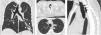

A 40-year old never-smoker, caucasian male, with no relevant past medical history and normal respiratory function tests, was observed due to the persistence of fever, cough, and sputum despite being treated with antibiotics for 5 days. A computed tomography was performed, which revealed a dilated trachea (26.2cm×28.5cm, as coronal and sagittal diameters), tracheal diverticula and bronchiectasis (Fig. 1). These findings were consistent with the diagnosis of Mounier-Kuhn Syndrome.